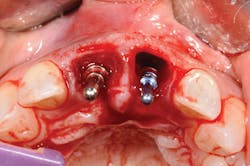

Figure 4: Implant was placed.

Figure 5: Implant and bone graft completed on No. 8, and implant placed on No. 9.

Extractions are a horrifying concept, yet in actuality there is pressure but no pain. Tooth No. 8, as predicted, shattered with the first touch (see Figure 3). The sound was terrible, a super loud snap. It took a moment for me to regroup, take a breath, and literally grieve the loss of my front tooth. It sounds ridiculous, but for me this was my true moment of loss, and then beginning. The prosthodontist decided that we would prepare each tooth individually, from start to finish. One tooth out, lots of drilling to remove the root, then synthetic bone-graft material mixed with my own bone (see Figure 4). As it happens, I was offered bovine bone, treated cow bone. As a nonmeat eater, there was not a chance I could handle that in addition to losing my two front teeth! Choosing synthetic was a personal option for me. Let your patients know there are cow, pig, cadaver, and synthetic materials available; it is a personal choice (see Figure 5).